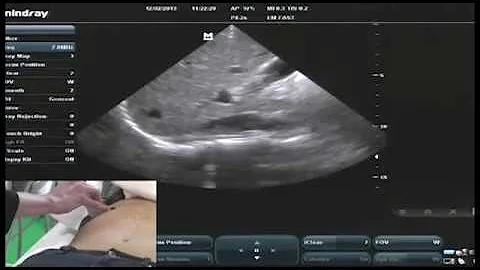

Step by Step instructions on Performing IVC Ultrasound in the Easiest way Possible!